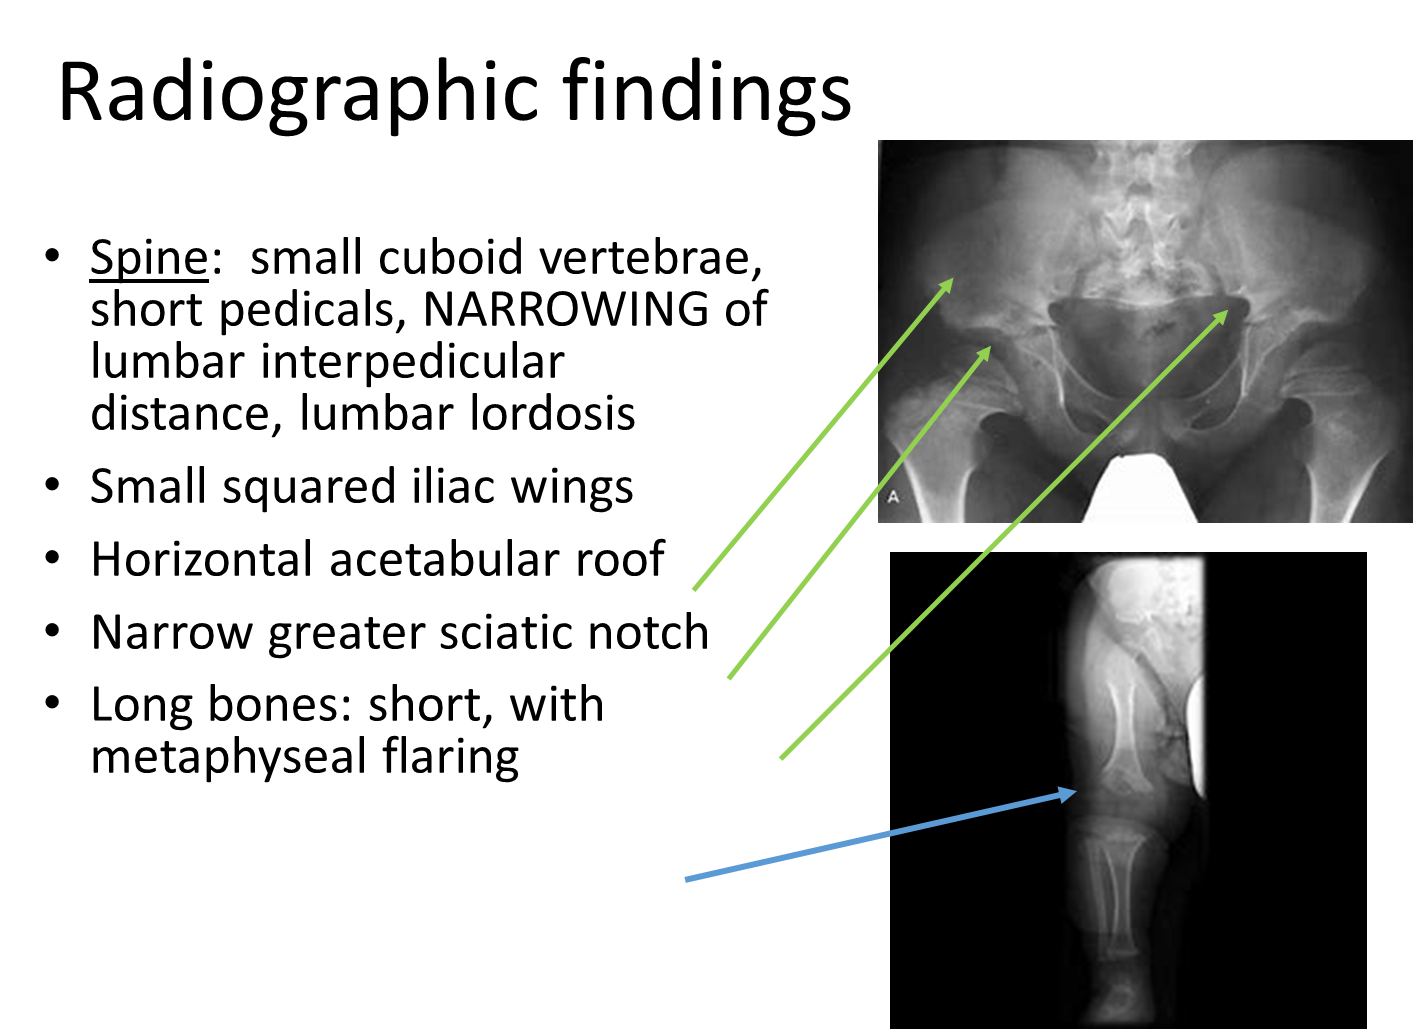

There are classic radiographic findings associated with achondroplasia

→ squared iliac wings

→ horizontal acetabular roof

→ narrow greater sciatic notch

→ long bones will be short and have metaphyseal flaring